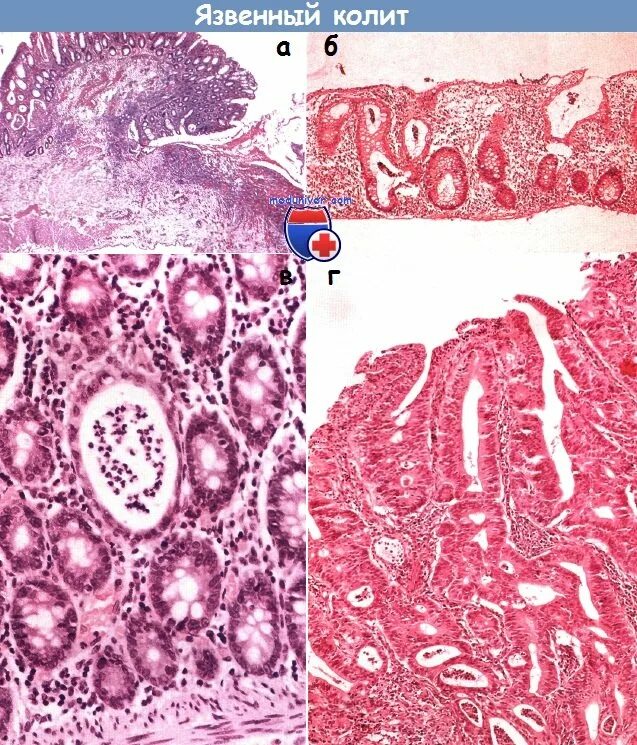

Причина язвенного колита у взрослых